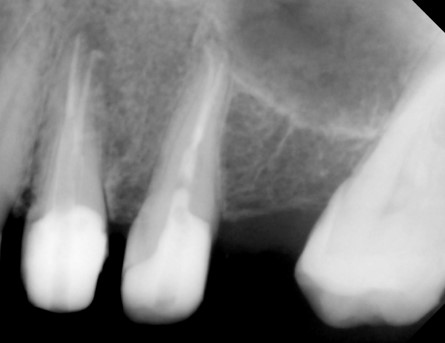

- Unhealthy pulp is removed. The length of the root canal is determined with the help of Electronic Apex locators as well as radiographs. The canals are then cleaned, enlarged and shaped with special caliberated instruments and disinfecting solutions.

- Periodic Radiographs (X rays) using digital RVG are taken during the treatment.

- Once the tooth is free of infection, the tooth is filled with a special root canal filling material like gutta percha and the access previously opened is sealed permanently with a Core filling.